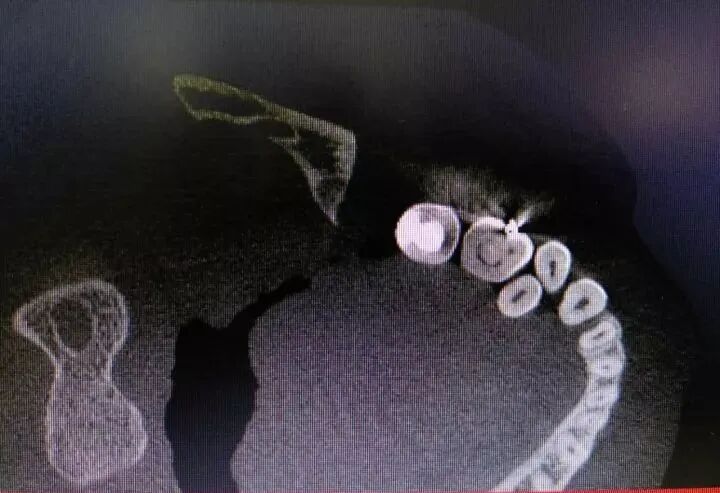

根管治疗前,在X线根尖片初步诊断患牙为牛牙症后,应常规进行CBCT检查,确定根管数目、形态及走向和炎症波及范围,掌握治疗难度,制定相应的治疗方案。

定位根管口:结合CBCT,显微镜的照明和放大功能来准确定位根管口;采用超声设备去除根管上段钙化物,同时,配合使用小号 C 锉和以及 EDTA 根管凝胶疏通根管;分别沿着不同根管口的方向插针拍摄X线片以进行核对。 -